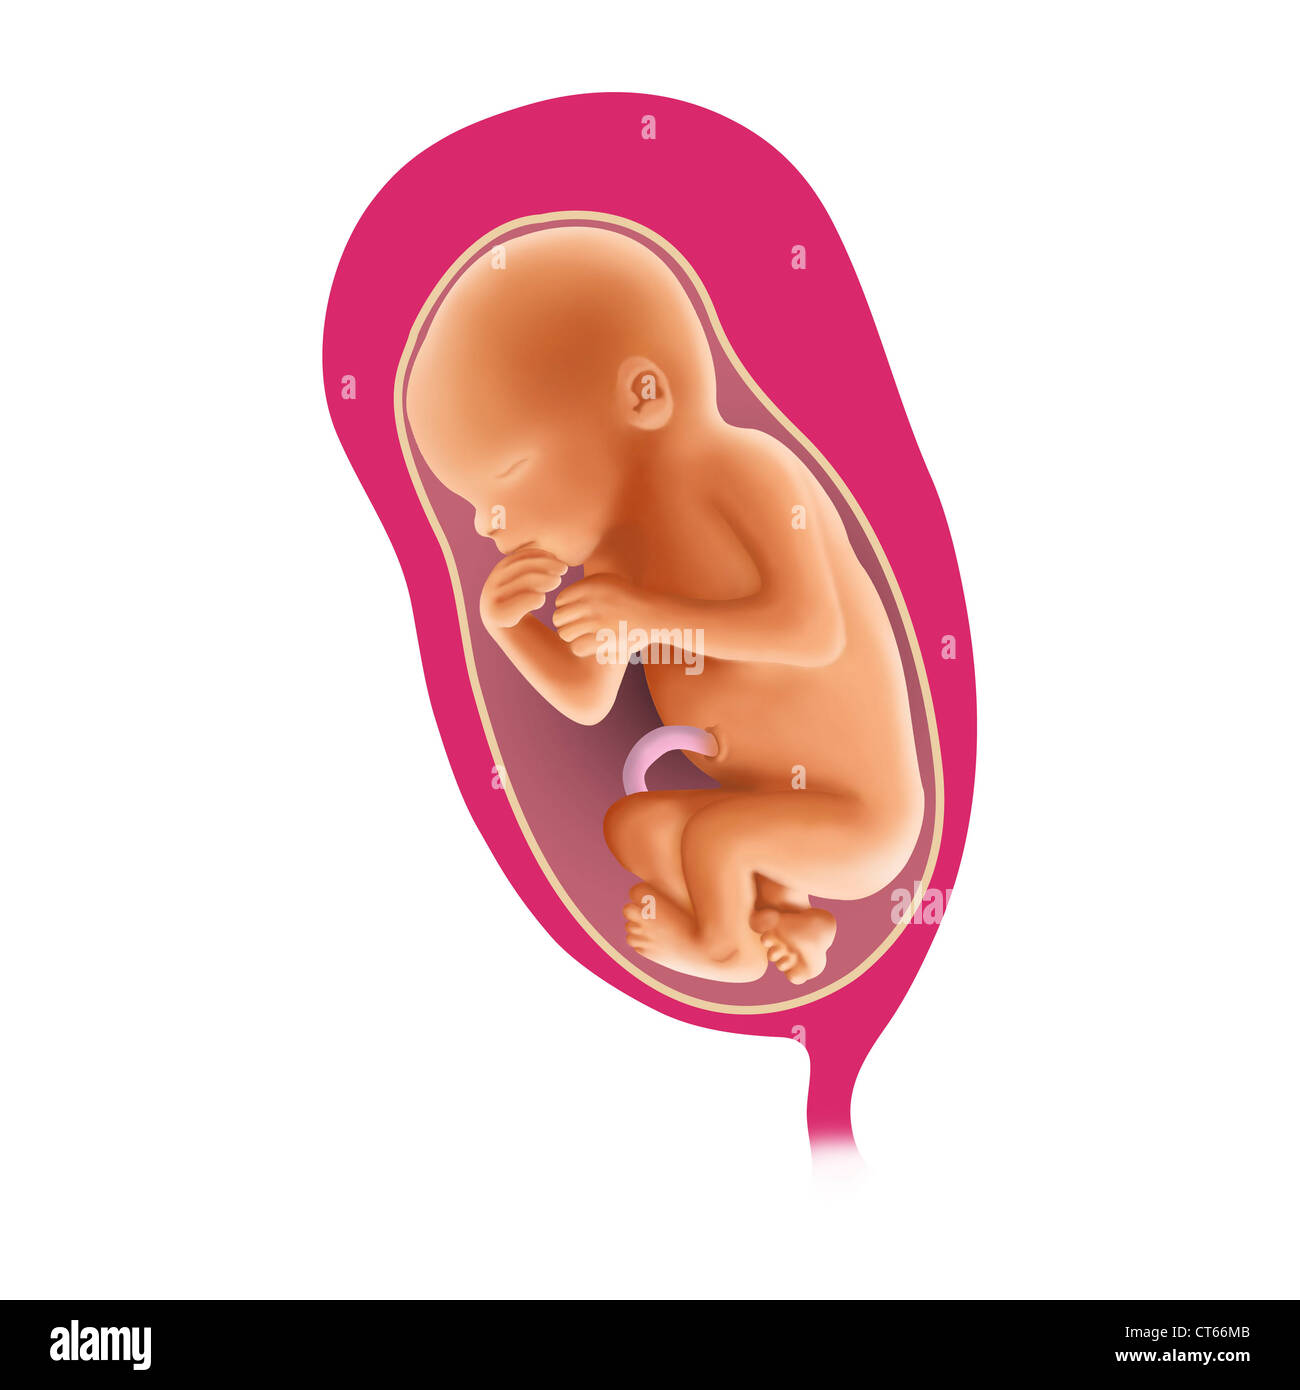

FETAL SHOULDER PRESENTATION Stock Photohttps://www.alamy.com/image-license-details/?v=1https://www.alamy.com/stock-photo-fetal-shoulder-presentation-49309466.html

FETAL SHOULDER PRESENTATION Stock Photohttps://www.alamy.com/image-license-details/?v=1https://www.alamy.com/stock-photo-fetal-shoulder-presentation-49309466.htmlRMCT66MA–FETAL SHOULDER PRESENTATION